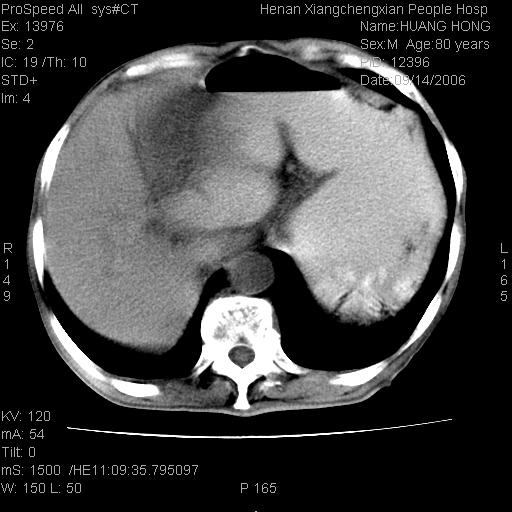

患者, 男, 80岁, 发现上腹部包块1年余,无其它不适.2006-9-14ct片是喝水后扫描2006-9-15ct片没喝水扫描![]() ![]() ![]() ![]() ![]() ![]() ![]() ![]() ![]() ![]() ![]() ![]() ![]() ![]() ![]() ![]() 以上是喝水片 以下是空腹片 ![]() ![]() ![]() ![]() ![]() ![]() ![]() ![]() ![]() ![]() ![]() ![]() ct:胰腺前方、肝脏与胃之间可见巨大类圆形囊性低密度影,大小约152mmx145mmx118mm,上缘平t11椎体上缘,下缘平l3椎体下缘,密度均匀,ct值15hu,其内呈多房分隔,囊壁薄且光滑,边界清晰,周围组织及器官明显受压。肝脏实质内未见异常密度影,胆囊未见异常,胰腺密度未见异常,脾脏大小、形态及密度未见异常,腹膜后间隙未见肿大淋巴结影。 印象:胰腺前方、肝脏与胃之间巨大类圆形囊性低密度影.性质待定。多考虑:.肠系膜巨大囊肿。 守望可可西里发言:支持楼主,考虑肠系膜囊肿,多为小肠系膜。 ysxyy发言:我总觉得这个病人虽然很像肠系膜囊肿,但还是应该强化一下; 下面这几幅图里肿块和主动脉的关系不太清,不知能否除外血管性来源? ![]() ![]() ![]() 病理结果:横结肠系膜间叶瘤.部分区域间质细胞增生活跃. 病理图片 ![]() 良性间叶瘤:是指由两种或两种以上的间叶组织所构成的混合性肿瘤.肿瘤仅发生在腹膜后和肠系膜,.前者较后者多发.良性间叶瘤常发生在肾或四肢,腹膜后较少见,各年龄均可发病.女多与男,预后较好,但术后易复法. 恶性间叶瘤:由两种以上恶性间叶组织成分组成. 光镜:肿瘤由脂肪/血管/平滑肌构成. 原贴地址: http://www.radinet.com.cn/forum_view.asp?forum_id=4&view_id=16217 ok |